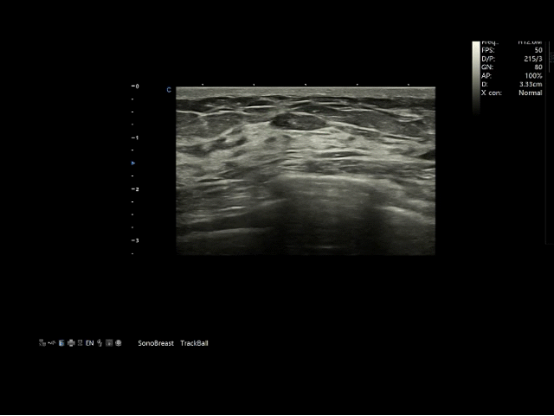

Today, CHISON provides a full range of AI-assisted ultrasound solutions across cardiology, OB/GYN, vascular, thyroid, breast, and point-of-care applications. Among them, SonoBreast, CHISON’s intelligent breast diagnostic software, received medical device certification in 2022—marking a significant milestone in the practical application of AI-assisted ultrasound diagnosis in China.

Powered by advanced deep learning technology, SonoBreast is trained on a vast dataset of annotated breast ultrasound images. It can automatically detect and analyze features such as lesion morphology, boundary characteristics, and blood flow patterns—shifting diagnosis from “seeing the image” to “understanding the pathology.”

The system can identify even millimeter-level microlesions and calcifications, and evaluates them in accordance with BI-RADS standards. By providing a clear, quantitative, and visualized assessment interface, SonoBreast supports more consistent, objective, and reproducible diagnostic decisions—reducing variability caused by physician experience or fatigue.